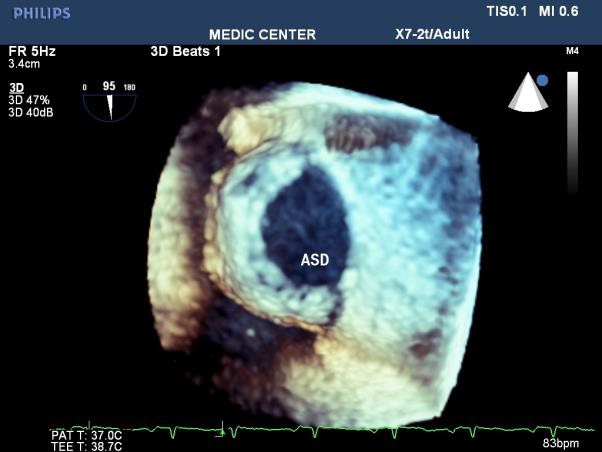

Among 204 Pts with ASD, The secundum defects account for approximately 78%, then primum ASDs 6%, sinus venosus ASDs 12%, multiple shunt ASD 4%, unroofed coronary sinus not seen. 3D TEE can assess the size of ASD and the circumferential rims to select Patients for Transcatether closure. Currently we perform ASD closure limited to ASDs less than 30mm and with at least 5mm of circumferential rims (Table 1).

The X-plan mode can be used to estimate the maximal diameter of defect in two orthogonal planes. Three-dimensional (3D) TEE imaging is an important adjunct to 2D imaging because multiplanar reconstruction ensures that the defect is measured accurately.

Three-dimensional (3D) TEE images can be rotated to demonstrate the defect from the RA or LA side in evaluating the secundum atrial septal defect rims. This improves understanding of their shape and relationships to surrounding intracardiac structures.

Multiple ASDs account only 4%, 3D TEE with wide sector can detect and visualize all the shunts through IAS (Figures 22-37).

Figure 23. 3DTEE Zoom mode presenting a secundum ASD (shape, size, all rims)

In the current area, Live 3D TEE is a usefull complementary tool in assessing the size, site, and shape of an ASD, its rims and realtions with neighboring structures. It is also helful in confirming the good positioning of a device and identifying the site of any residual shunt next to device closure [11].

We always display a true en face view of the defect from the left atrium so that its dimensions can be accurately measured [12]. Three dimensional 3D TEE visualizes clearly the shape and the rims in a view only, that previously were obtained only by many consecutive 2D views. Review of 72 suscessful cases of ASD device closure demonstrates the size of ASD and its rims were always recorded and measured on the 3D TEE view from the left atrium. Three patients with unsuscessfull ASD device closure related to short aortic rim ( from 0 to 3mm ).

Three-Dimensional (3D) TEE enables improved visualization of ASDs using unique en face representation of the interatrial septum. Three-Dimensional (3D) TEE provides the valuable information including shape, size of defect, its rims prior to perform transcatether device closure.